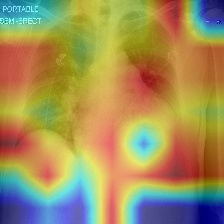

We produce localization maps by computing Ablation-CAMs for our models, applied to over 100 images from the COVIDx test split. These maps highlight image regions deemed important by the model for classifications. Figures 2(a) and 2(b) show three example COVID-positive images and localization maps computed on the Swin-B model (200-epoch). Figure 2(c) shows corresponding maps produced by the ResNet-50 baseline model on the same images.

The localization maps produced by Swin Transformers highlight the lung area, successfully focusing on the ground glass pattern, consolidation and peripheral linear opacities used by human doctors for diagnosis (Cleverley et al., 2020). In contrast, maps produced by the ResNet-50 are less successful, highlighting irrelevant areas such as shoulders and arms, sometimes missing the lungs entirely.